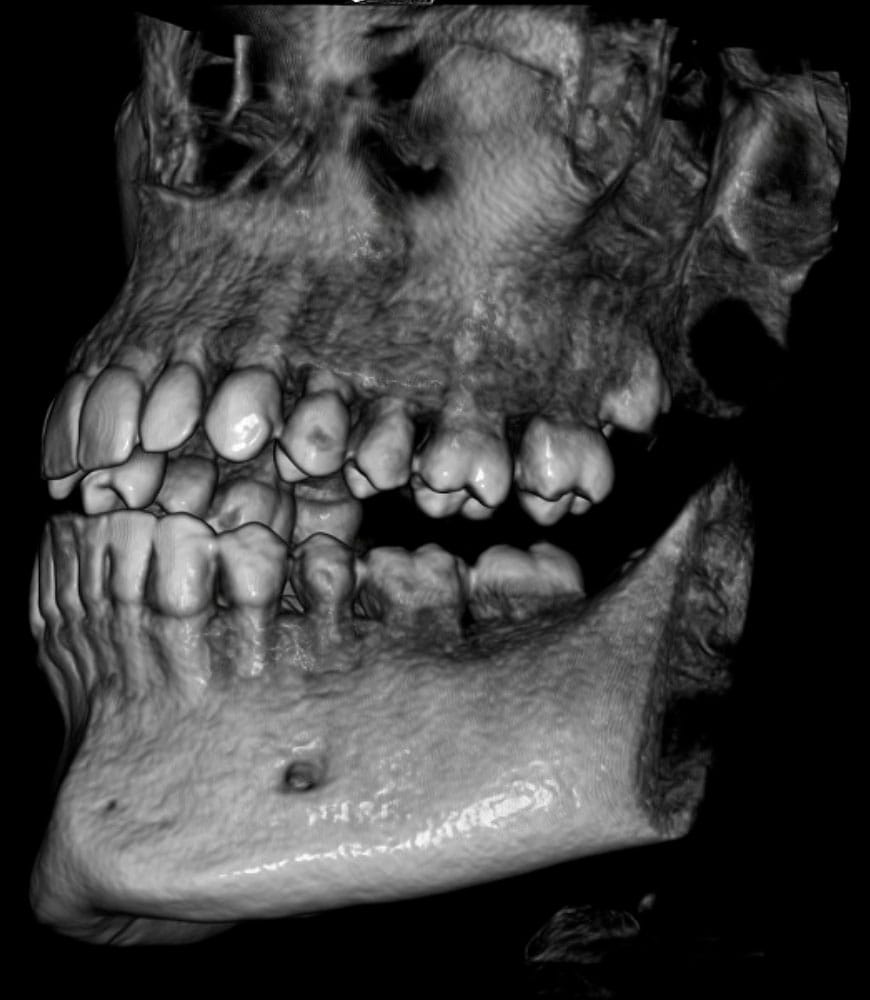

Mala praxis en radiografías dentales

Errores en Radiografías Dentales: Un Riesgo en el Diagnóstico y Tratamiento

Las radiografías dentales son fundamentales para un diagnóstico preciso y la planificación de tratamientos. Sin embargo, una mala praxis en su interpretación o realización puede llevar a errores graves, como diagnósticos incorrectos, tratamientos innecesarios o la omisión de patologías importantes.

Entre los errores más comunes están la mala calidad de la imagen, exposición innecesaria a radiación, interpretación errónea de caries o infecciones, y fallos en la identificación de estructuras anatómicas. Estas negligencias pueden derivar en extracciones innecesarias, colocación incorrecta de implantes o la progresión de enfermedades sin detectar.